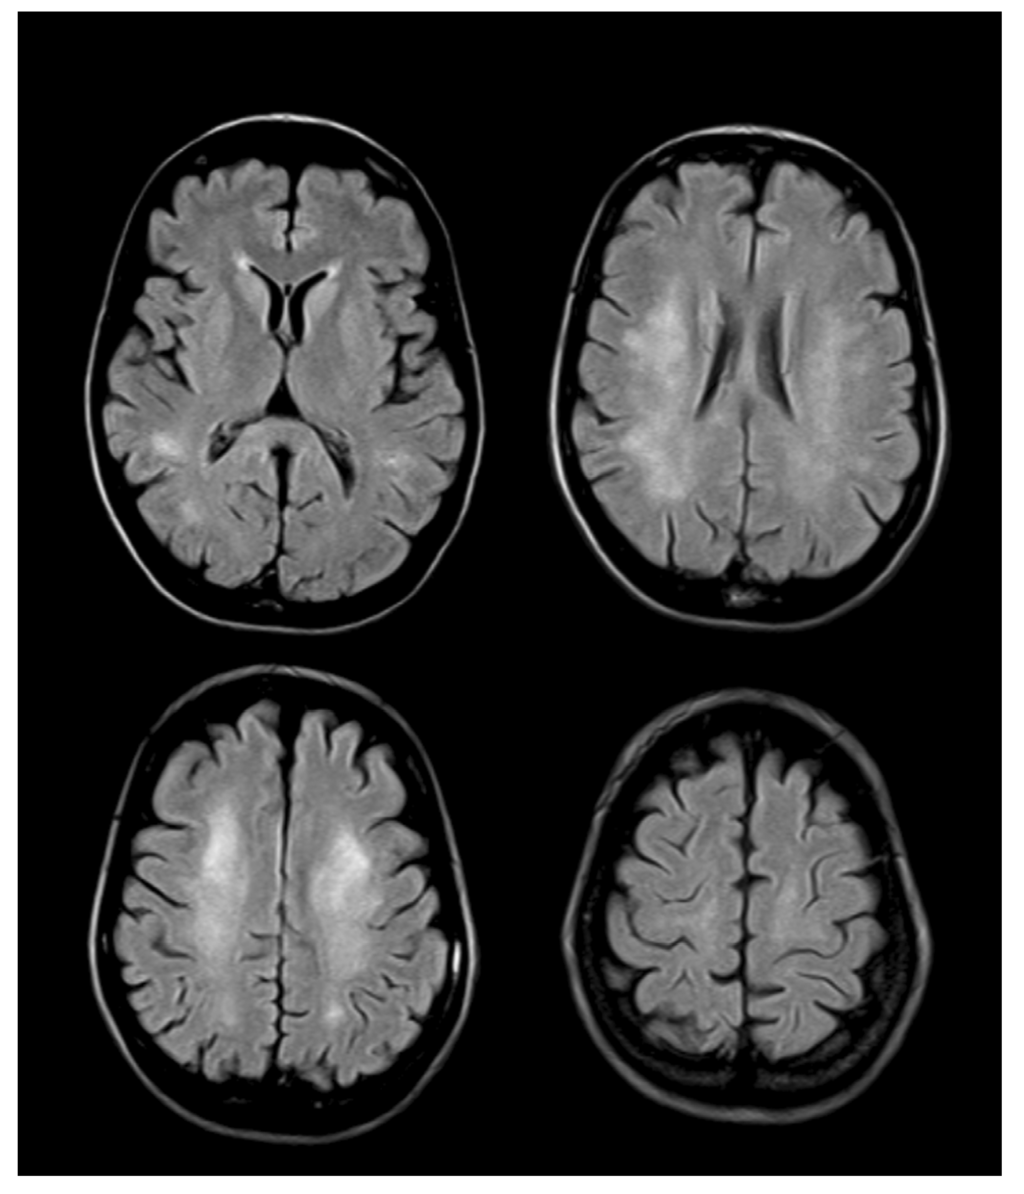

4. Neuroimaging

- Lovblad, K.; Ramelli, G.; Remonda, L.; Nirkko, A.C.; Ozdoba, C.; Schroth, G. Retardation of myelination due to dietary vitamin B12 deficiency: Cranial MRI findings. Pediatr. Radiol. 1997, 27, 155–158. [Google Scholar] [CrossRef]

- Kori, S. Hyperintense splenium in vitamin B12 deficiency. Neurol. India 2005, 53, 377–378. [Google Scholar] [CrossRef]

- De Lau, L.M.; Smith, A.D.; Refsum, H.; Johnston, C.; Breteler, M.M. Plasma vitamin B12 status and cerebral white-matter lesions. J. Neurol. Neurosurg. Psychiatry 2009, 80, 149–157. [Google Scholar]

- Scott, T.M.; Tucker, K.L.; Bhadelia, A.; Benjamin, B.; Patz, S.; Bhadelia, R.; Liebson, E.; Price, L.L.; Griffith, J.; Rosenberg, I.; et al. Homocysteine and B vitamins relate to brain volume and white-matter changes in geriatric patients with psychiatric disorders. Am. J. Geriatr. Psychiatry 2004, 12, 631–638. [Google Scholar]

- Graber, J.J.; Sherman, F.T.; Kaufmann, H.; Kolodny, E.H.; Sathe, S. Vitamin B12-responsive severe leukoencephalopathy and autonomic dysfunction in a patient with “normal” serum B12 levels. J. Neurol. Neurosurg. Psychiatry 2010, 81, 1369–1371. [Google Scholar] [CrossRef]